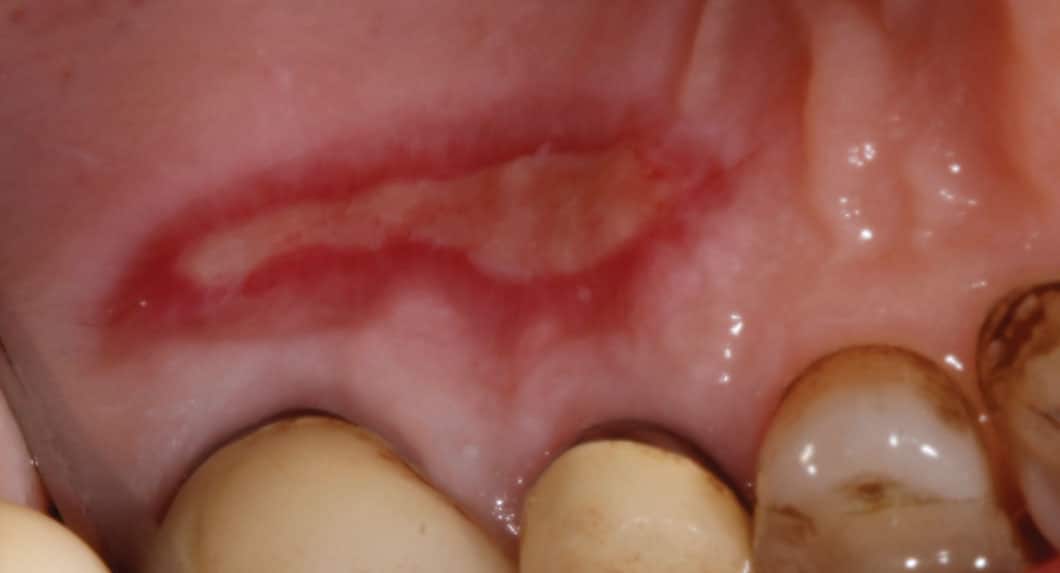

Return to "Soft Tissue Graft Alternatives for Treating Mucogingival Defects" FIGURE 1. Palatal wound healing at the donor site via secondary intention after soft tissue graft harvest. Next Previous